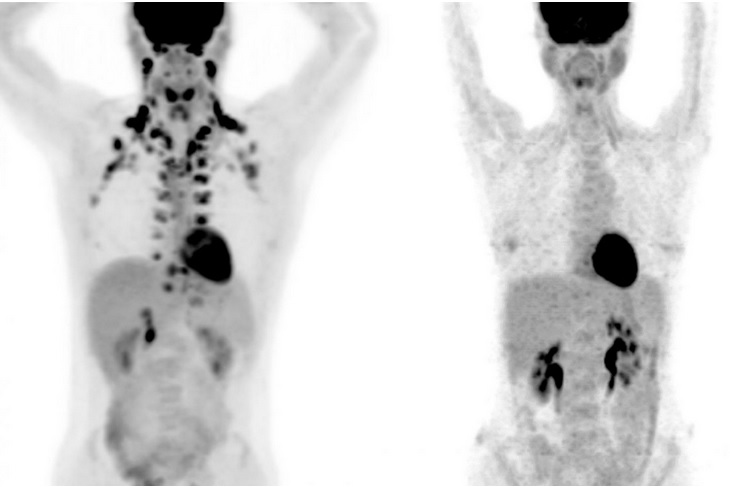

La graisse brune -ou tissu adipeux brun-, contrairement à la graisse blanche, qui stocke des calories, brûle de l'énergie. De nombreuses équipes à la recherche de traitement de l’obésité espèrent parvenir à transformer la mauvaise graisse en tissu adipeux brun. Cependant ce n’est que récemment qu’a été suggérée une association possible entre la graisse brune (à gauche sur visuel) et une meilleure santé. Ensuite, il est difficile d'identifier les personnes qui présentent plus de graisse brune car ce tissu est plutôt situé profondément à l'intérieur du corps.

Il s’agit de la plus large étude menée sur le sujet, soit sur l’association entre la graisse brune et toute une série de résultats de santé. En effet, bien que la graisse brune ait été étudiée pendant des décennies chez les nouveau-nés et les animaux, ce n'est qu'en 2009 que les scientifiques se sont rendu compte qu'elle pouvait être également trouvée en bonne quantité chez certains adultes, généralement autour du cou et des épaules. Depuis, les chercheurs se sont efforcés de comprendre l’action de ces cellules graisseuses particulières, à la capacité de brûler des calories. Avec des limites techniques néanmoins, car la graisse brune n'apparaît que sur les PET scans, un type d'imagerie médicale coûteux qui utilise des radiations. Donc il est difficile de soumettre les participants à ce type d’examen.